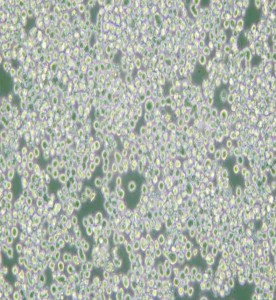

RPMI 8226人多發(fā)性骨髓瘤外周血B淋巴細(xì)胞主圖

RPMI 8226人多發(fā)性骨髓瘤外周血B淋巴細(xì)胞

中文名稱 :人多發(fā)性骨髓瘤外周血B淋巴細(xì)胞

細(xì)胞形態(tài) :淋巴母細(xì)胞樣

生長(zhǎng)特性 :懸浮細(xì)胞